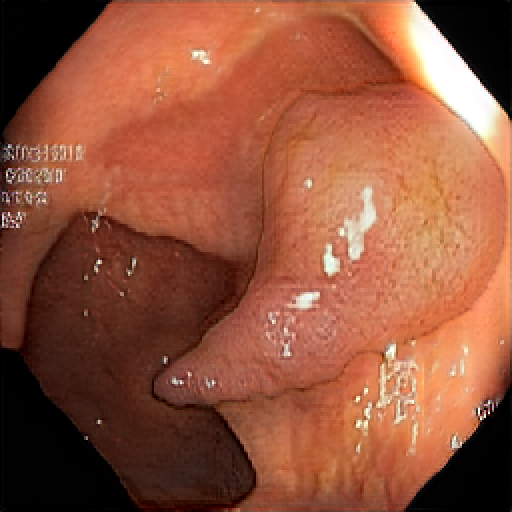

We have used a polyp dataset published with HyperKvasir dataset [51], which consists of polyp findings extracted from endoscopy examinations. HyperKvasir contains polyp images with corresponding segmentation masks annotated by medical experts. We use only this polyp dataset as a case study because of the time and resource-consuming training process of the SinGAN-Seg pipeline. However, the SinGAN-Seg model and pipeline can be used for any segmentation dataset.

A few sample images and the corresponding masks of the polyp dataset in HyperKvasir are shown in Fig 2. The polyp images are RGB images. The masks of the polyp images are single-channel images with white () for true pixels, which represent polyp regions, and black () for false pixels, which represent clean colon or background regions. In this dataset, there are different sizes of polyps. The distribution of polyp sizes as a percentage of the full image size is presented in the histogram plot in Fig 3, and we can observe that there are more relatively small polyps compared to larger polyps. Additionally, a subset of this dataset was used to prove that the performance of segmentation models trained with small datasets can be improved using our SinGAN-Seg pipeline, and the whole dataset was used to show the effect of using SinGAN-Seg generated synthetic images instead of a large dataset which has enough data to train segmentation models. In this regard, this dataset was used for two purposes: